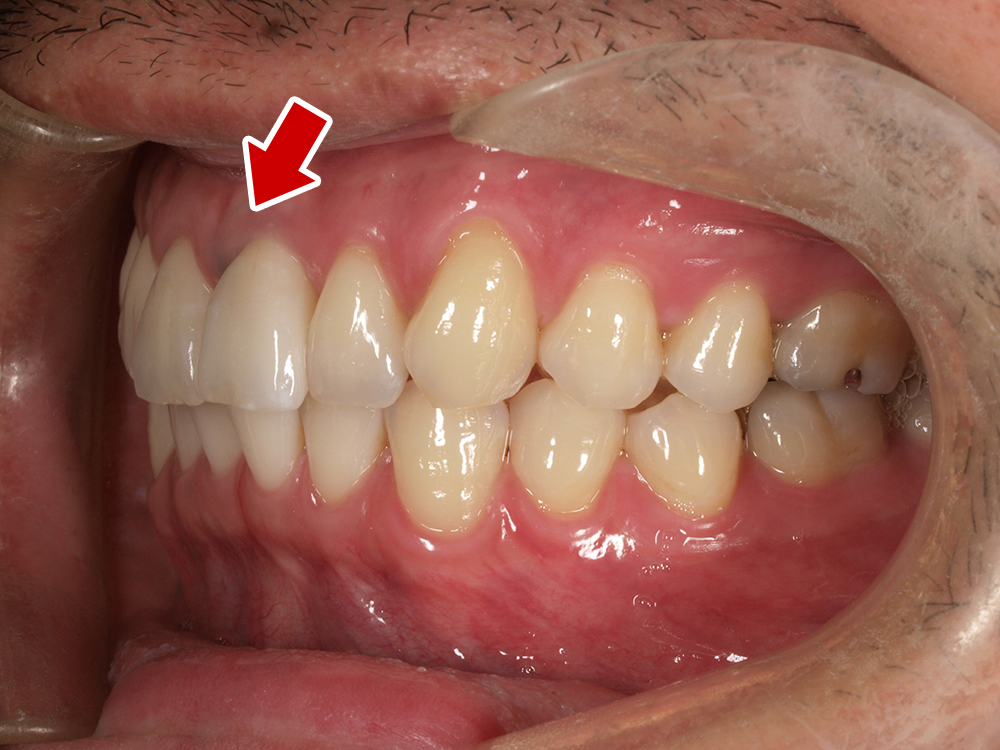

45歳 男性 医療関係者紹介

- 主訴

- 右前歯が取れた(右上2)

- 処置内容

-

1本インプラント埋入+再生療法

抜歯即時埋入⇒抜歯を行い、同時にインプラント埋入(即時埋入)

- 治療費用

- 上顎:約40万円(税込)

- 治療期間

- 約11か月

- リスク

- 上部構造物、仮歯の破折、術後の腫れ(3日)、人工歯根脱落リスクがあります